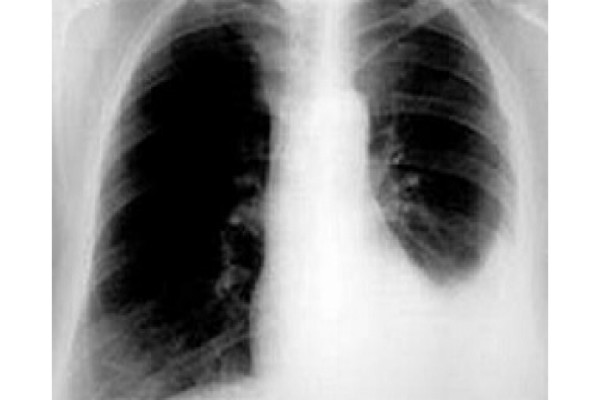

- Sau đó bạn có thể được các bác sĩ yêu cầu chụp X-quang hoặc chụp CT để chẩn đoán bệnh chính xác hơn nếu nghi ngờ có dấu hiệu tràn dịch màng phổi.